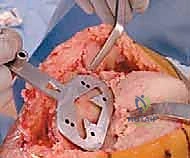

الدليل المصور: خطوات جراحة استبدال مفصل الركبة الكلي بالإسمنت خطوة بخطوة

تُعد هذه الجراحة عملاً فنياً هندسياً ودقيقاً، يتطلب مهارة جراحية استثنائية. بفضل تقنيات الجراحة المجهرية واستخدام أحدث الأدوات، يضمن الأستاذ الدكتور محمد هطيف دقة متناهية في كل خطوة. نستعرض هنا توثيقاً دقيقاً من داخل غرفة العمليات (Intraoperative Steps):

5. تطبيق الإسمنت الع